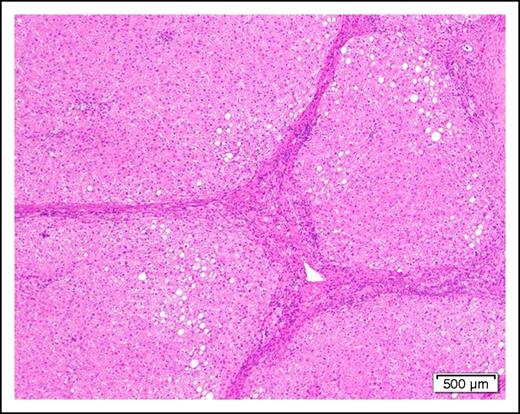

A 58-year-old man with cirrhosis (Figure 2) of the liver attributable to chronic alcohol abuse is found to have AML with the mixed-lineage leukemia translocation t(4;11)(q21;q23). He has evidence of portal hypertension as manifested by mild ascites and edema of the lower extremities. The serum albumin is mildly low at 3.0 g/dL and the prothrombin time and partial thromboplastin time are slightly prolonged.

Photomicrograph of a cirrhotic liver illustrating well developed fibrous septa separating irregular regenerative nodules. The hepatocytes show mild steatosis (hematoxylin and eosin stain, original magnification ×40).